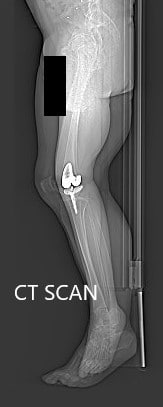

Postoperative X-ray showing AP and lateral views of the right knee

The recovery of the patient was unremarkable. She was able to walk the same day of the surgery. The pain was well managed with oxycodone and acetaminophen. Aspirin was used for DVT prophylaxis. The sutures were removed uneventfully.

The initial active range of motion was from 5 to 90 degrees which gradually increased to 3 to 120 degrees after a month of physical therapy. She demonstrated a full range of motion without any pain at her 3 months follow up visit. The patient was now back in her routine. She was happily doing yoga and enjoyed fencing as she did before the onset of pain.